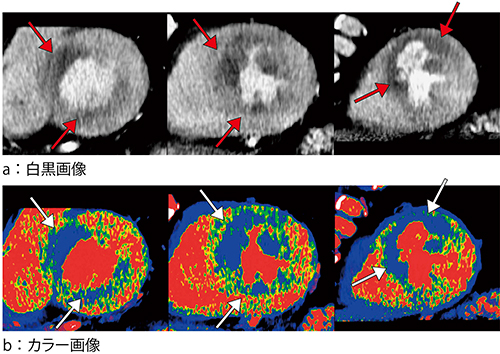

CTでも虚血部位の診断は可能であるが,MRIと比べるとコントラスト分解能が劣る。そこで当院では,CT値の高い部分に暖色,低い部分に寒色を用いたカラー表示にすることで,コントラストをつけて診断能を向上させている(図2)。また,大動脈のCT値を測定し,その造影効果に応じた半定量的カラーマップを作成することで,三枝病変など全体の血流が落ちている症例でも虚血を検出することができる。

図2 術前CTP画像

左から心基部,心中部,心尖部。カラー表示にすることで虚血部位 (→)が明瞭に描出される。前壁中隔に内膜下優位の心筋血流低下を認める。